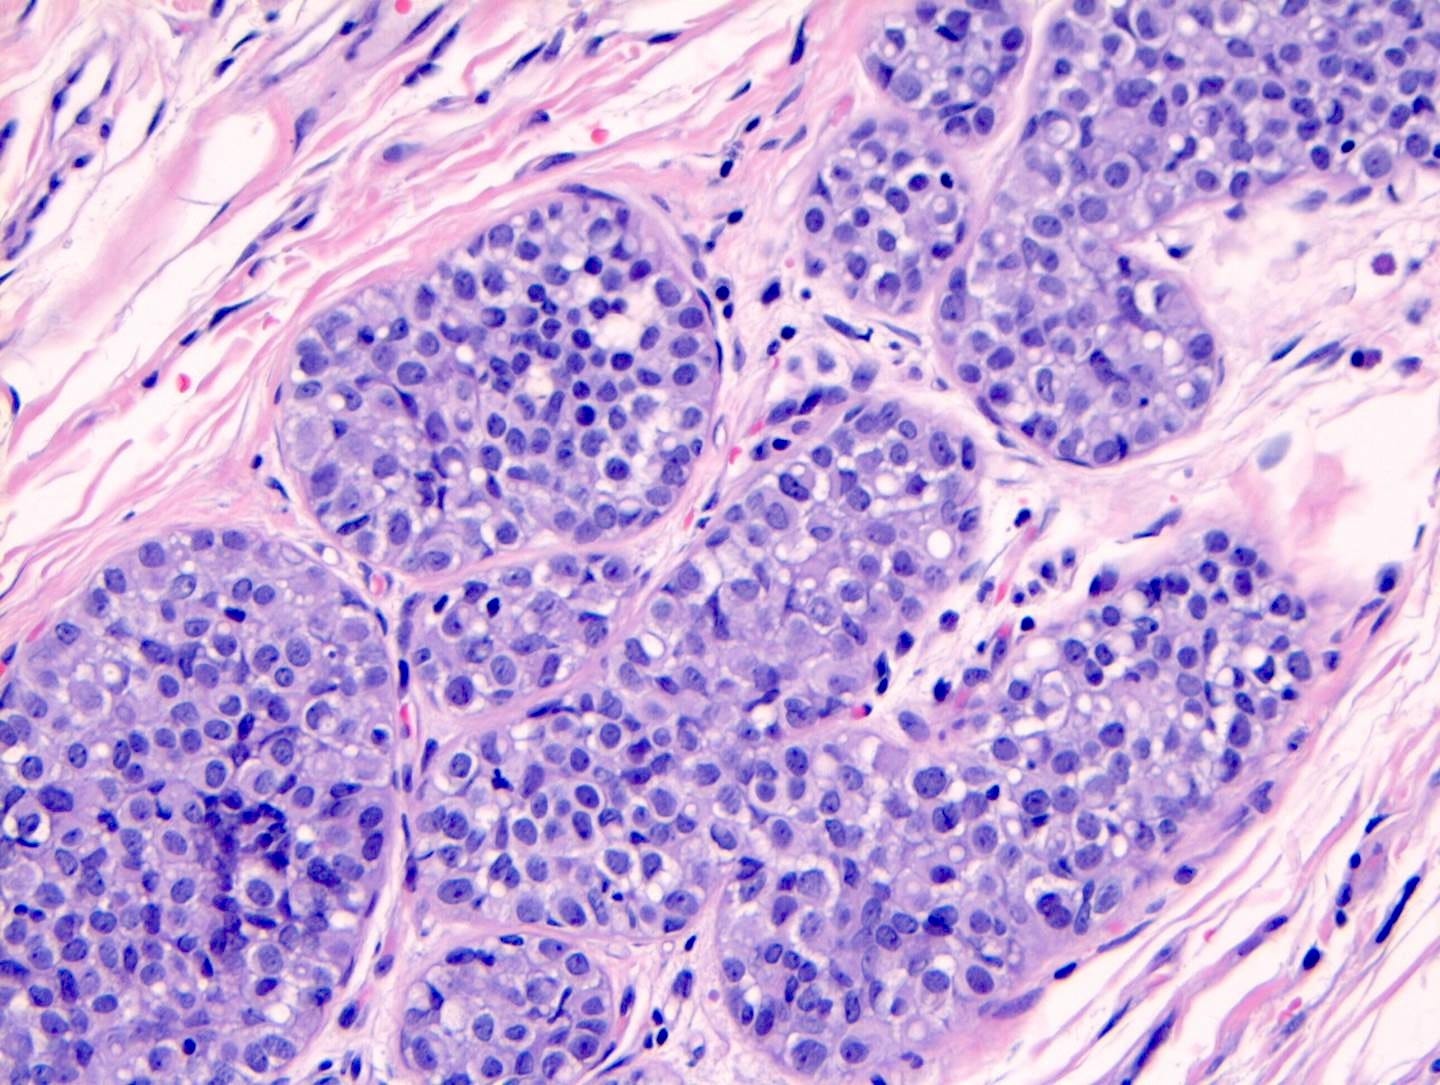

Infiltrating duct carcinoma (IDC) of no special type - microscopic images

The premalignant precursors of invasive duct carcinoma of no special type are DCIS (ductal carcinoma in situ) and classic LCIS (lobular carcinoma in situ). In addition, we speculate that there may be unidentified precursors based on molecular patterns of change without microscopic changes, although this is unproven.

Precursor of IDC - ductal carcinoma in situ (DCIS)

Ductal carcinoma in situ (DCIS) is a neoplastic proliferation of breast ductal epithelial cells within the ductal-lobular system with malignant microscopic features but without evidence of invasion through the epithelial basement membrane or myoepithelial cell layer into the surrounding stroma.

DCIS is a precursor of infiltrating duct carcinoma of no special type. It is also a precursor of tubular carcinoma, cribriform carcinoma, male invasive carcinoma and neuroendocrine carcinoma-small cell type.

DCIS includes a heterogeneous group of lesions in terms of microscopic appearance, molecular alterations, biomarker expression profile and biologic potential for progression to invasive carcinoma. It is divided into low grade (less aggressive) DCIS and high grade DCIS. Normal breast tissue appears to transform to only one of these entities through two distinct molecular pathways (i.e. high grade DCIS does not typically arise from low grade DCIS). Low grade DCIS shows frequent chromosomal losses at 16q. High grade DCIS shows frequent losses at 8p and gains at 17q and has a similar molecular profile as invasive breast cancer.

DCIS - microscopic images